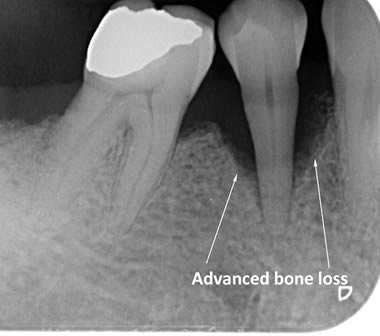

The diagrams below show the different stages of gum disease

Periodontitis is a more advanced stage of gum disease where there has been damage to the bone which supports the teeth. If left untreated periodontitis leads to more and more bone loss until the teeth start to become loose and eventually fall out by themselves or need to be extracted by a Dentist.

The main cause of gum disease is plaque. Plaque consists of millions of bacteria which live on and around the teeth and gums. These bacteria produce toxins which damage the gums. To begin with the gums start to peel away from the teeth and “pockets” form. As the bacteria penetrate deeper into these “pockets” they then start to cause damage to the bone which holds the teeth in. As more bone loss occurs the teeth start to become increasingly looser until they eventually start to fall out one by one.